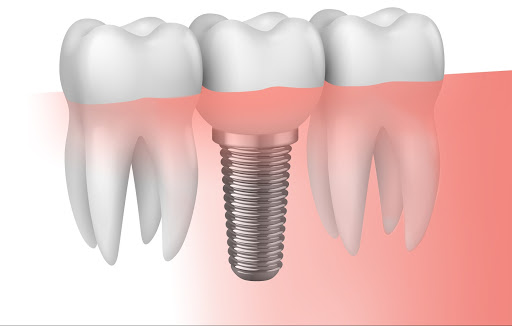

Un implante dental es un elemento metálico, similar a un tornillo, que sustituye la raíz del diente natural perdido. Se coloca mediante un tratamiento quirúrgico en el hueso maxilar y/o mandibular, por debajo de la encía, y permite la colocación de una corona, puente o prótesis. Por tanto, al reemplazar la raíz y corona del diente natural, actúa como tal y se evita la pérdida de hueso maxilar.

Es un procedimiento quirúrgico, por lo que se precisa anestesia local. La colocación es como si de un tornillo se tratara. Se va perforando el hueso con varios diámetros de tornillos hasta la colocación del definitivo. Posteriormente se finaliza con la suturación de la encía para cerrar la herida.

La osteointegración de un implante, es decir, la adaptación del implante al hueso maxilar o mandibular, suele durar entre 3 y 6 meses.

El material por el que está compuesto un implante es primordial en el éxito de éste. El más común es el titanio, aunque también los hay de zirconio.